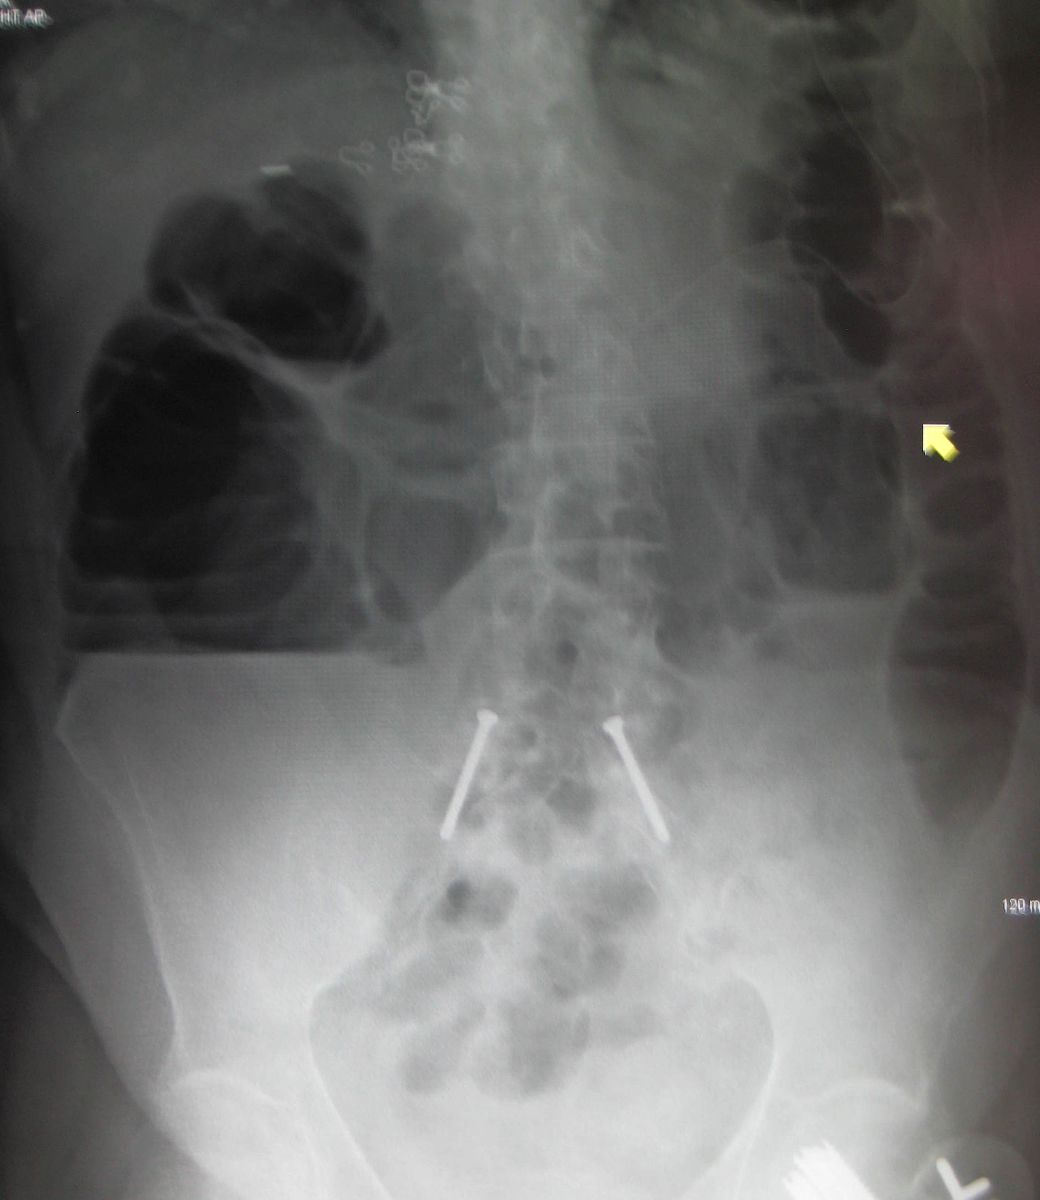

Example 3

Diagnosis

Large Bowel Obstruction